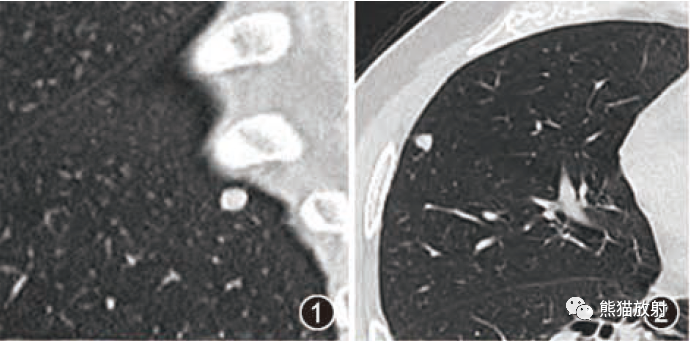

【影像表现】 钡灌肠:直肠与乙状结肠起始部可见不规则充盈缺损(图1箭头),肠管见偏心性狭窄;粘膜皱襞紊乱,纠集(图2、3箭头)。 CT:直肠壁不均匀增厚,见软组织影突入直肠腔内,增强扫描中度强化,周围脂肪间隙欠清楚,直肠后方可见肿大淋巴结(箭头)。肝脏体积增大,肝内密度欠均匀,可见多发弥漫不均匀低密度区,增强扫描病灶显示更加清楚,呈多发结节样低密度影,脾周及胆囊窝周围可见少量液性低密度影。

X线:增生型:主要表现为充盈缺损,充盈缺损周边的的粘膜破坏中断或见小溃疡。气钡双重造影可显示肿块的轮廓。溃疡型:主要表现为腔内突起的龛影和“半月征”。浸润型:主要沿肠壁环形生长,使肠壁增厚,肠腔狭窄,可见狭窄段粘膜呈锯齿状。混合型:常有两种以上的表现混合存在。